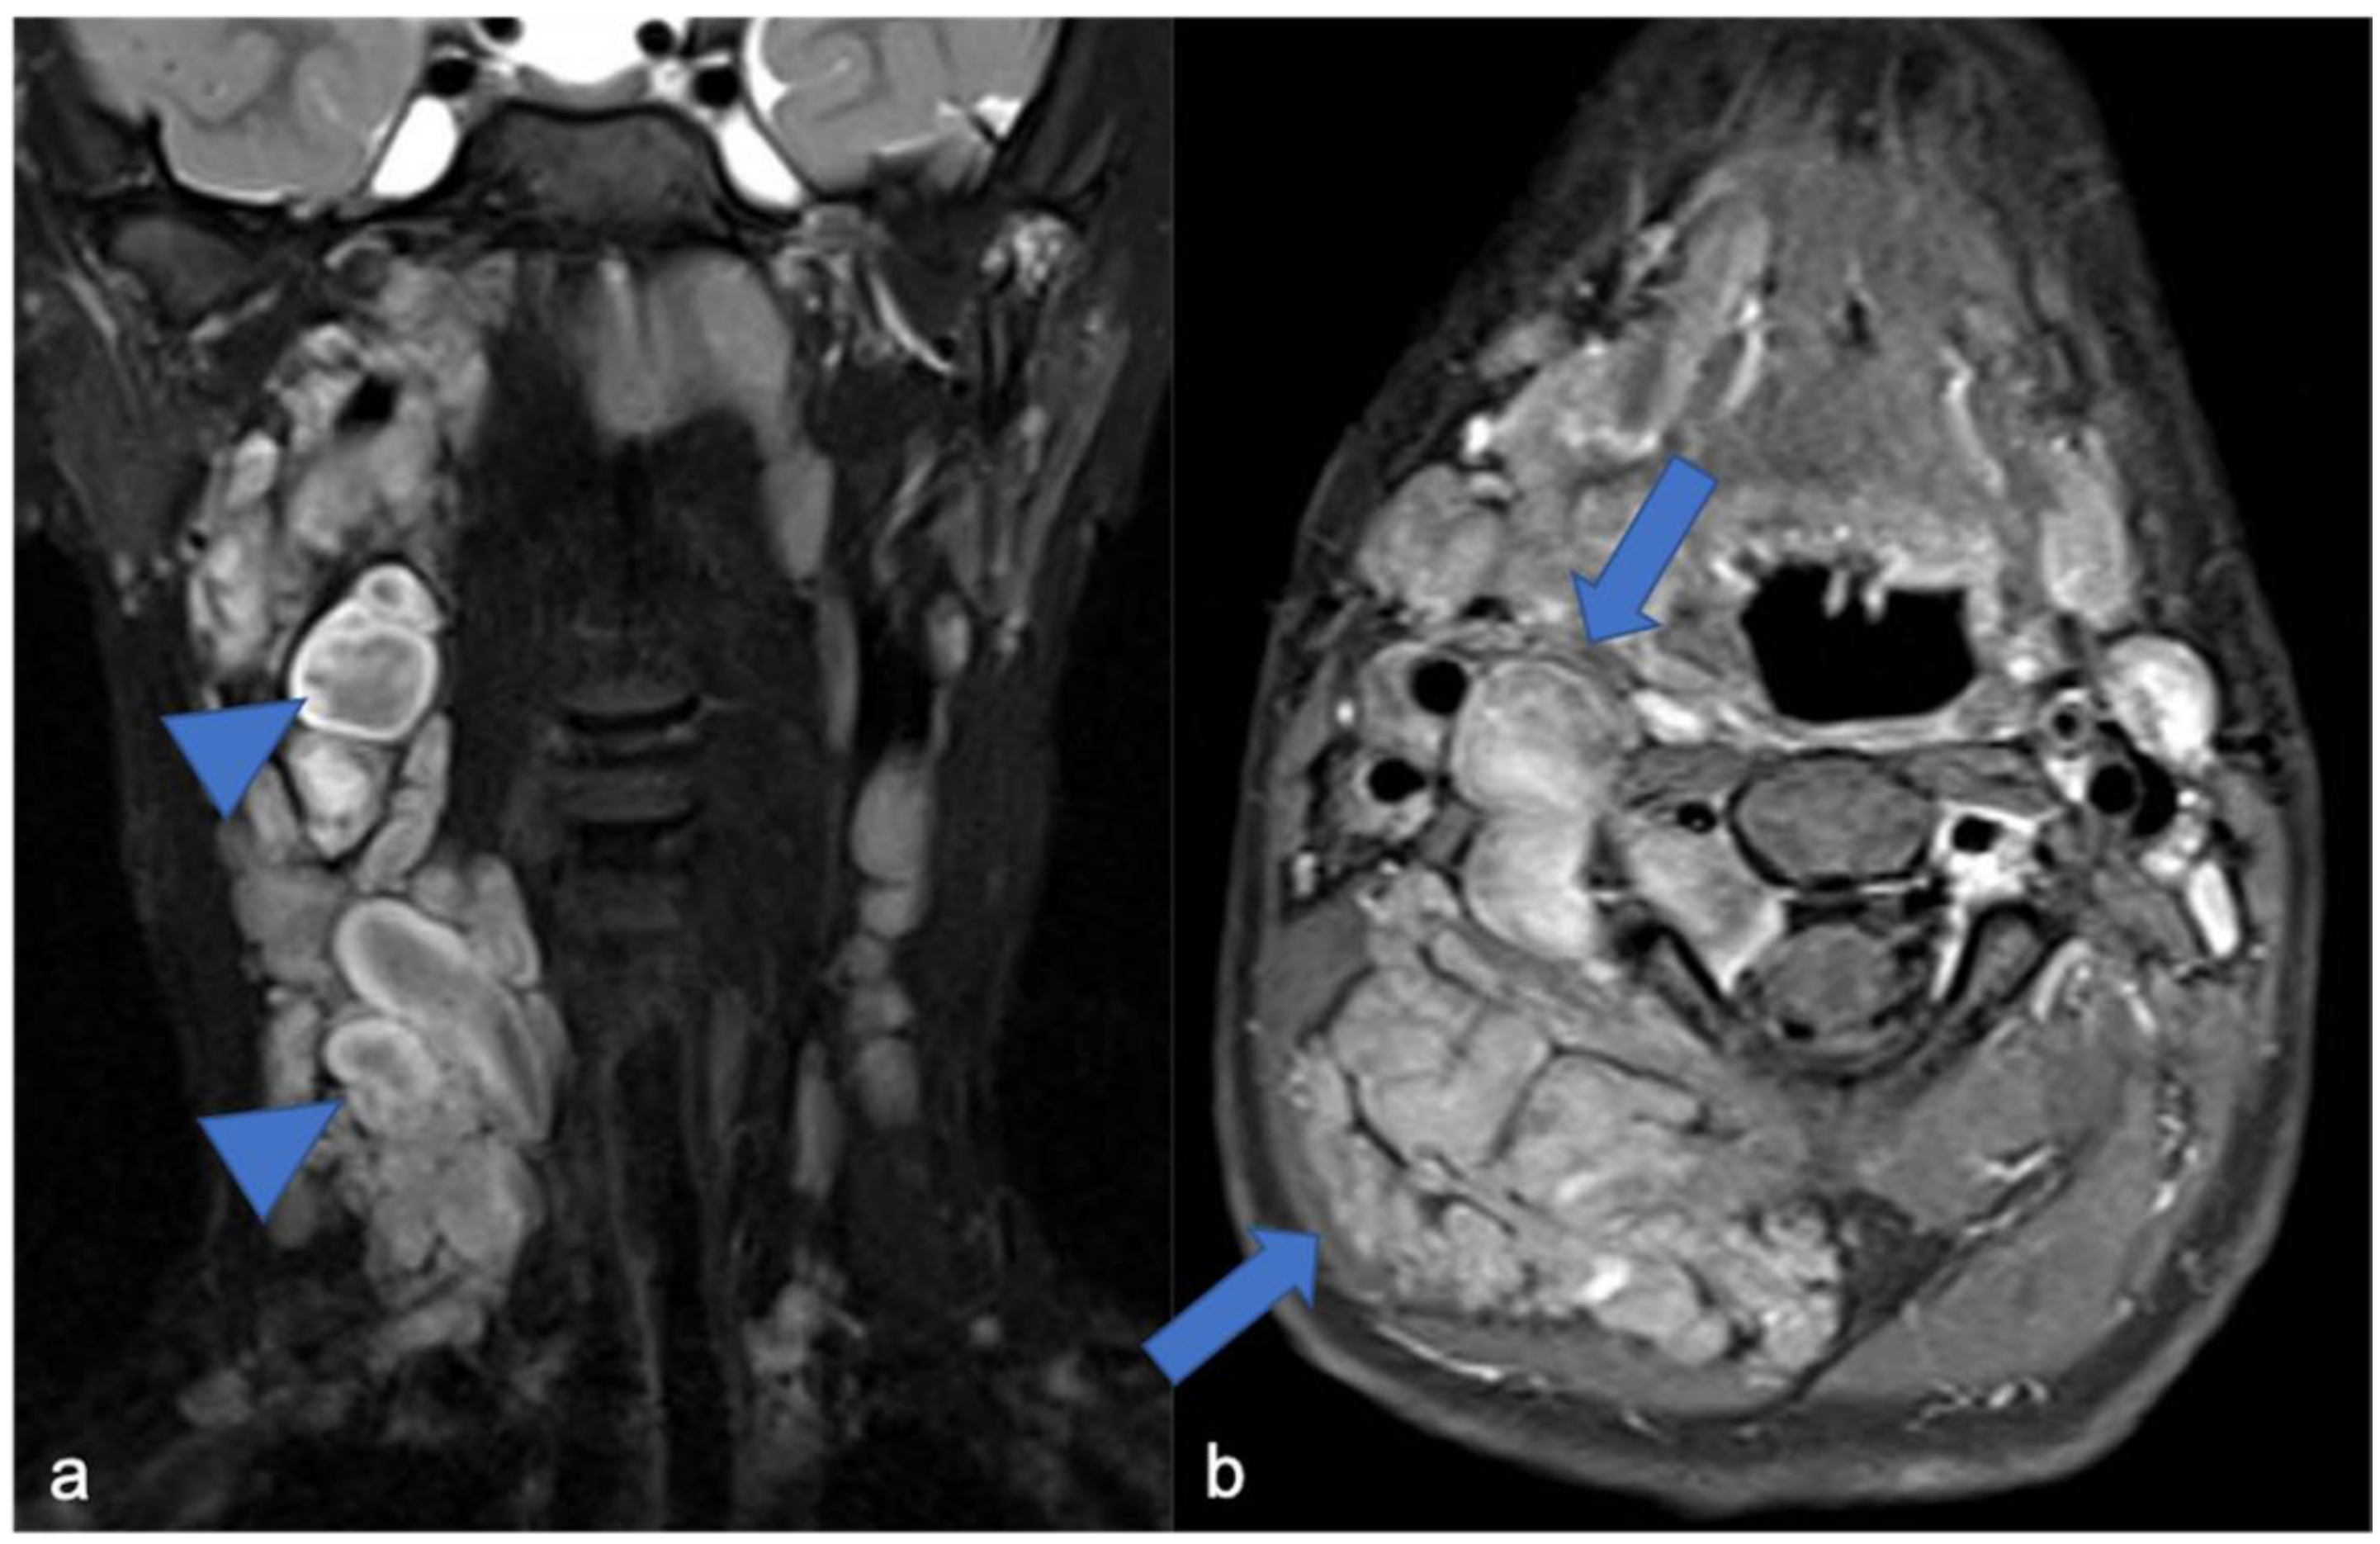

Figure 11.

(a) Coronal «saturated» T2-weighted and (b) axial post-contrast «saturated» T1-weighted images. Multiple neurofibromas (arrows) in a pediatric patient with NF1. The “target sign” (central area of hypointensity in T2) can be observed (arrowheads).